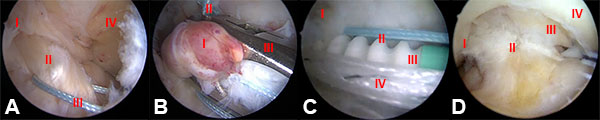

Se identifican los haces anteromedial (AM) y posterolateral (PL) del LCA. Se realizan los puntos a través del haz anteromedial utilizando una pinza FastPass Scorpion (Arthrex) con una sutura FiberWire número 2 (Arthrex) desde el extremo distal intacto en un patrón alternante de tipo Bunnell hacia el extremo proximal (fig. 5A). Se realizaron 3 pases hasta que se alcanzó el extremo proximal. Los puntos para el haz posterolateral se realizaron de forma similar con una sutura FiberWire número 2 (Arthrex) (fig. 5B). Luego se confeccionan pequeñas microfracturas en la cara interna del cóndilo femoral lateral, utilizando un punzón sin afectar la huella del LCA, para estimular la médula ósea como estrategia de aumento biológico que intenta promover la quimiotaxis, la proliferación celular y/o la producción de matriz en el sitio de la reparación del LCA y el menisco ayudando a superar las limitaciones de cicatrización.29-33 Con la rodilla en 90° de flexión, se crea un portal anteromedial inferior accesorio para el abordaje directo a la huella femoral. Se creó un túnel de 3,5 por 20 mm, en el origen femoral del haz AM. Las suturas de FiberWire del haz anteromedial se pasan a través del ojal de un anclaje ventado BioCompuesto SwiveLock de 4,75 mm (Arthrex) precargado con Tigertape 2 mm (Arthrex) que luego se utilizó como internal brace (fig. 5C). De esta forma, el primer anclaje se fija en el fémur hacia el origen anteromedial con la rodilla en 90° de flexión, mientras se tensa el resto del LCA hacia la pared para evitar la formación de un gap. Este procedimiento se repitió luego para el haz posterolateral con las suturas FiberWire y un anclaje ventado BioCompuesto SwiveLock de 4,75 mm que se insertó a 110° de flexión. Logrando de esta manera una fijación y tensado independiente de cada haz del LCA. Finalmente se cortan los extremos libres de las suturas de reparación con un cortador de sutura de extremo abierto (Arthrex).

Por último, se constata bajo visión artroscópica la posición final del LCA reinsertado en su huella femoral (fig. 5D).

Figura 5: Imagen artroscópica de rodilla derecha, vista desde el portal anterolateral, con el paciente en posición supina y la rodilla a 90 ° de flexión. A) La sutura del haz anteromedial (AM) con FiberWire N1. I: Pared Medial Cóndilo Ext. II: Remanente Haz AM. III: Sutura. IV: LCP. B) La sutura del haz posterolateral (PL) con TigerWire No.1. I: Remanente Haz PL. II: Sutura. III: Pinza Scorplo. C) La colocación del ancla ventado BioCompuesto SwiveLock 4,75 mm para fijar el haz anteromedial con el TigerTape 2mm (Internal Brace) carcado en el ojal. I: Pared Medial del Cóndilo Ext. II: Sutura Haz AM. III: SwiveLock 4.75 mm Biocompuesto. IV: TigerTape 2mm (Internal Brace). D) La reinserción del LCA en su huella femoral. I: Cóndilo Femoral Externos. II: LCA Reinsertado. III: LCP. IV: Cóndilo Femoral Interno.